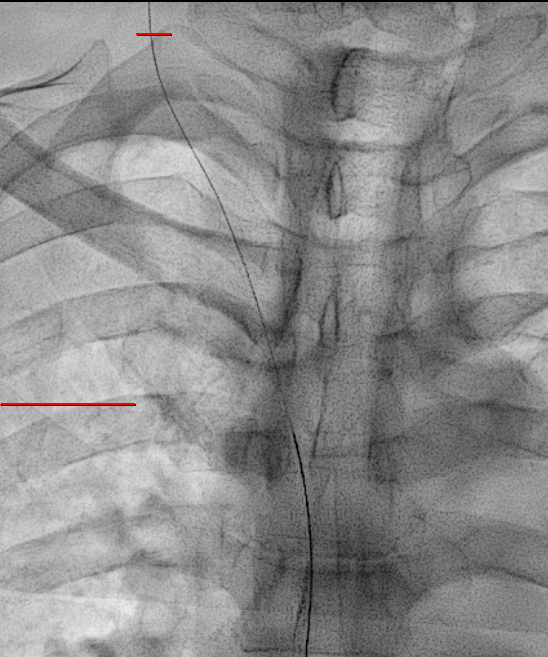

X-ray 를 보면서 이 와이어가 적절한 위치로 가는지 잘 봐야합니다.

대부분의 경우는 상대정맥으로 잘 내려가지만 내려가는 경로 상 기정맥(Azygos vein)이나 내흉정맥(Internal thoracic vein)이 있을 수도 있거든요.

이런 정맥들로 잘못 들어가게 되면 정맥포트가 금방 기능을 잃어버립니다.